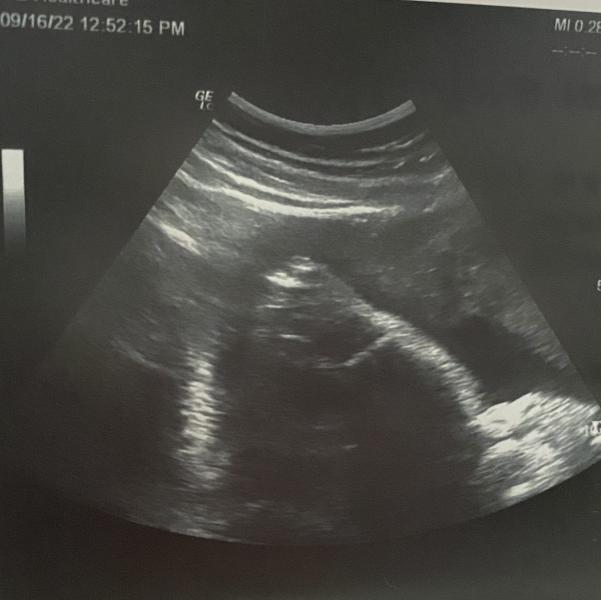

Сегодня на УЗИ увидели обвитие, но не тугое.

Врач сказала, что это даже хорошо, значит пуповина не короткая, короткая может в родах привести к кровотечению, потому что с малышом потянет плаценту!🙈